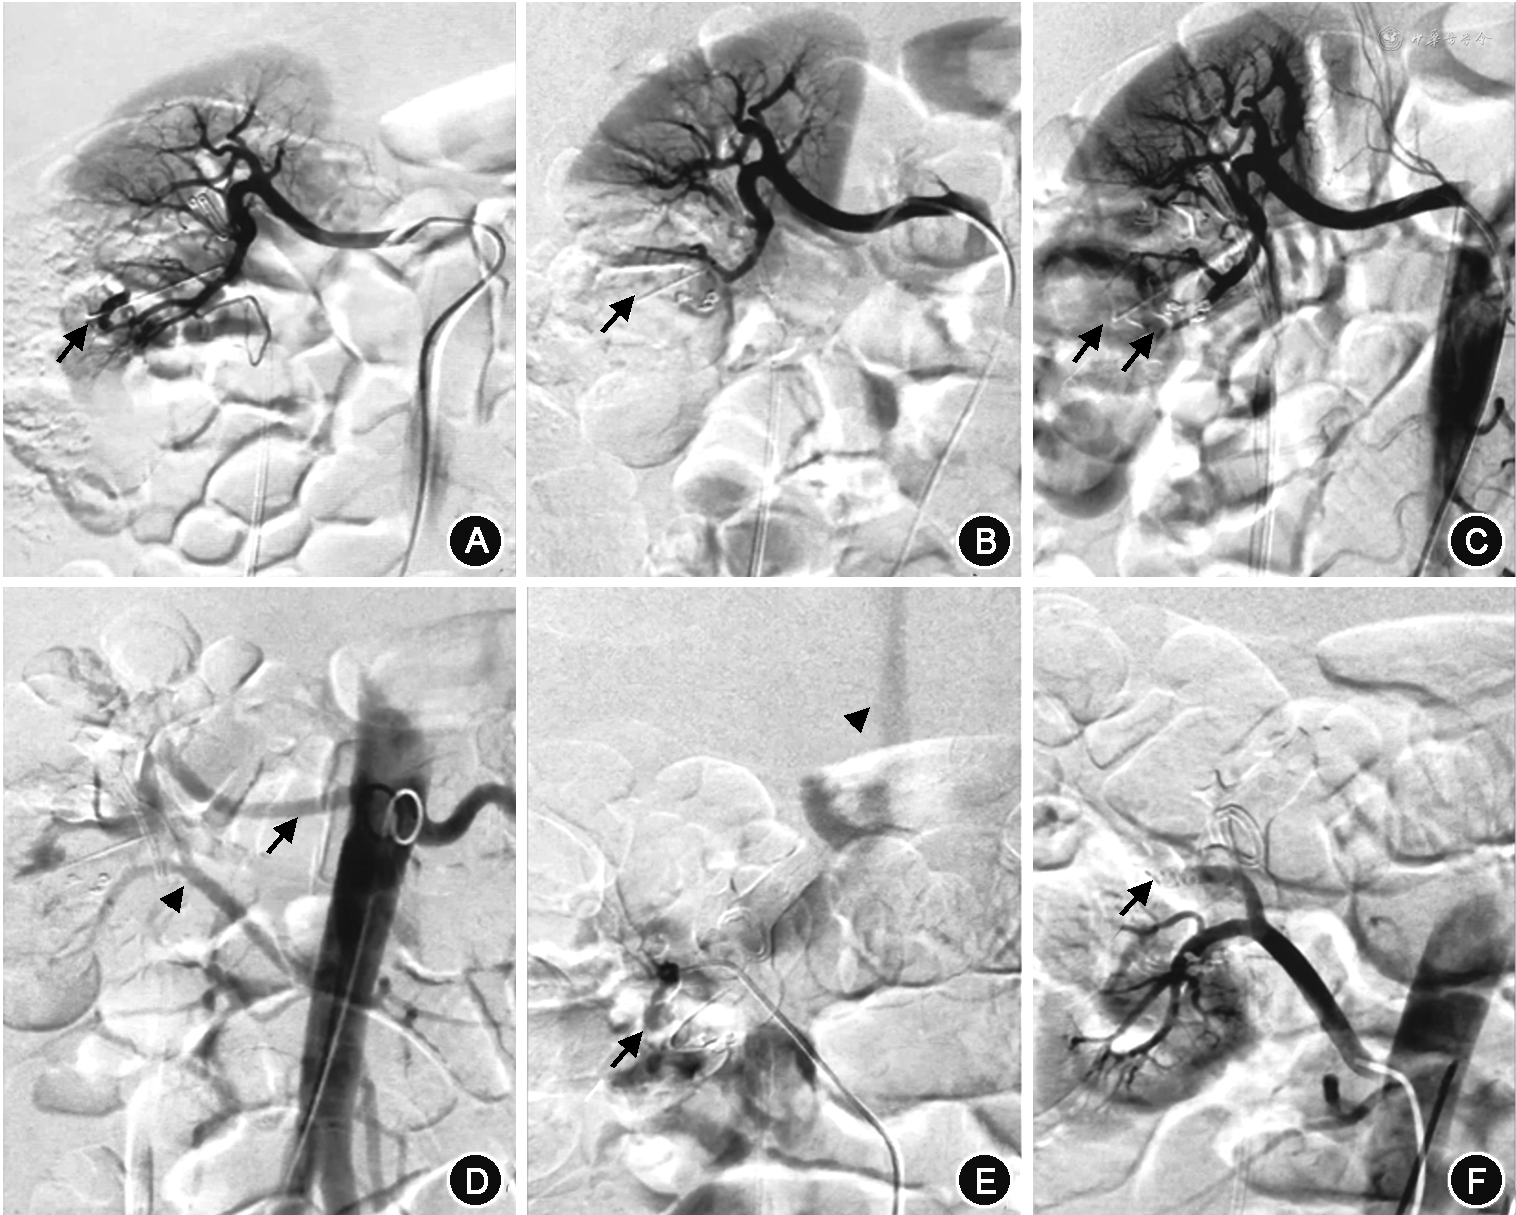

2. 诊断与治疗方法:27例患者均在保守治疗无效后急诊局麻下经皮股动脉穿刺插管至患肾动脉,行选择性肾动脉造影,初次造影结果为阴性,未发现出血部位。再保守治疗1~3 d无效后,经反复肾动脉造影,最后均发现血管损伤病变。其中15例假性动脉瘤(图1A),4例动静脉瘘(图1B),8例假性动脉瘤合并动静脉瘘(图1C)。23例行2次、4例行3次肾动脉造影。分析原因,其中一味追求选择性肾动脉造影,遗漏副肾动脉供血所致出血5例12次(图2、3);两处以上出血,只处理一处出血3例6次;初次未发现出血病变,第二次才发现者17例36次;选择栓塞物不当2例4次。诊断明确后同时行超选择栓塞术,栓塞当时即复查肾动脉造影,27例显示病变完全栓塞,出血点消失,术后患者严重血尿症状立即得到改善,1周内肉眼血尿及腰部不适症状全部消失,尿色转清,血红蛋白持续稳定,拔出肾造瘘管后患者出院;其中5例出现栓塞后综合征,表现为低热、腰部胀痛不适等症状,给予退热、止痛等对症处理后症状消失。